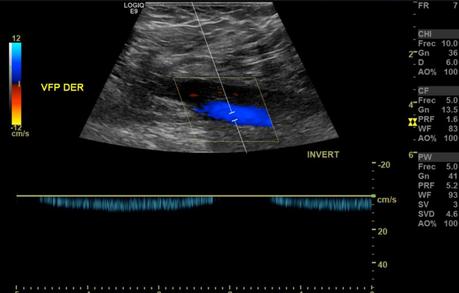

Se realizaron múltiples barridos ecográficos con transductor lineal de 9 MHz en escala de grises, Doppler color y espectral, con paciente en decúbito supino, efectuando valoración del sistema venoso superficial y profundo, observando siguientes hallazgos:

En el sistema venoso profundo, la valoración de las venas femoral común, femoral, femoral profunda, poplíteas, todas ellas presentaron flujo espontáneo y respiratorio fasico unidireccional con adecuada competencia valvular.